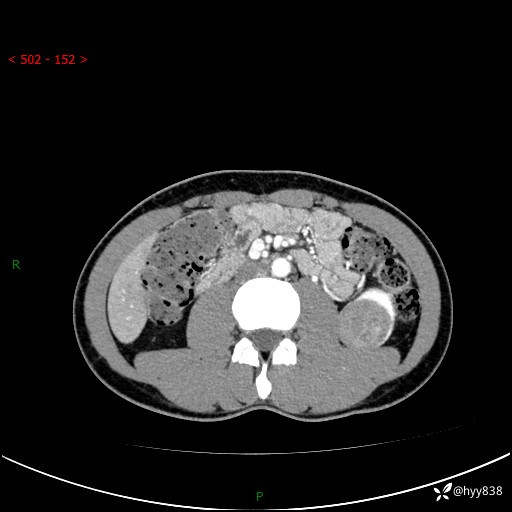

年轻男性,发现左肾占位1天。“非好病例”我不发,误诊率高---(有结果)

现病史:患者昨日中午进食后出现明显腹痛,腹泻,在我院急诊科行补液及对症治疗,双肾输尿管彩超提示左肾占位(5.2*4.3cm),平素无明显腰痛,无再发肉眼血尿等情况,现为求处理左肾占位,遂来我院,门诊以左肾占位收治入院。 患者起病以来,精神、食欲、睡眠尚可,大便可,小便如上,体力体重无明显下降。

双肾CT平扫+增强(三期)